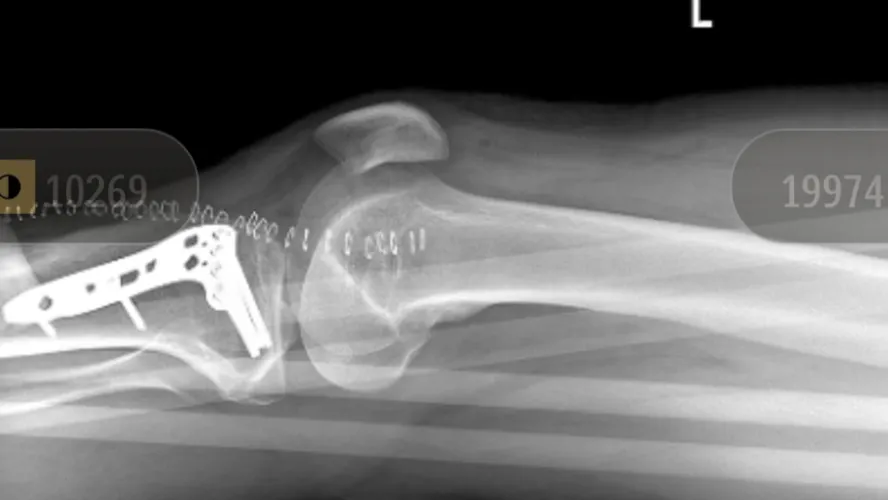

Chris was rushed to the hospital, where he spent four days admitted — two days in the trauma ward and two days recovering post-operation. He suffered a crushed left leg and has already undergone multiple surgeries. Doctors have made it clear that this will be a long road to recovery. They are estimating at least eight months of recovery and rehabilitation. Right now, Chris is in a wheelchair and using a walker as he begins the difficult journey of healing.

Looks like a good job on the tibial plateau fracture. I’ve assisted many such cases with flouro . I’m so glad you are getting the help you need. ✌️❤️